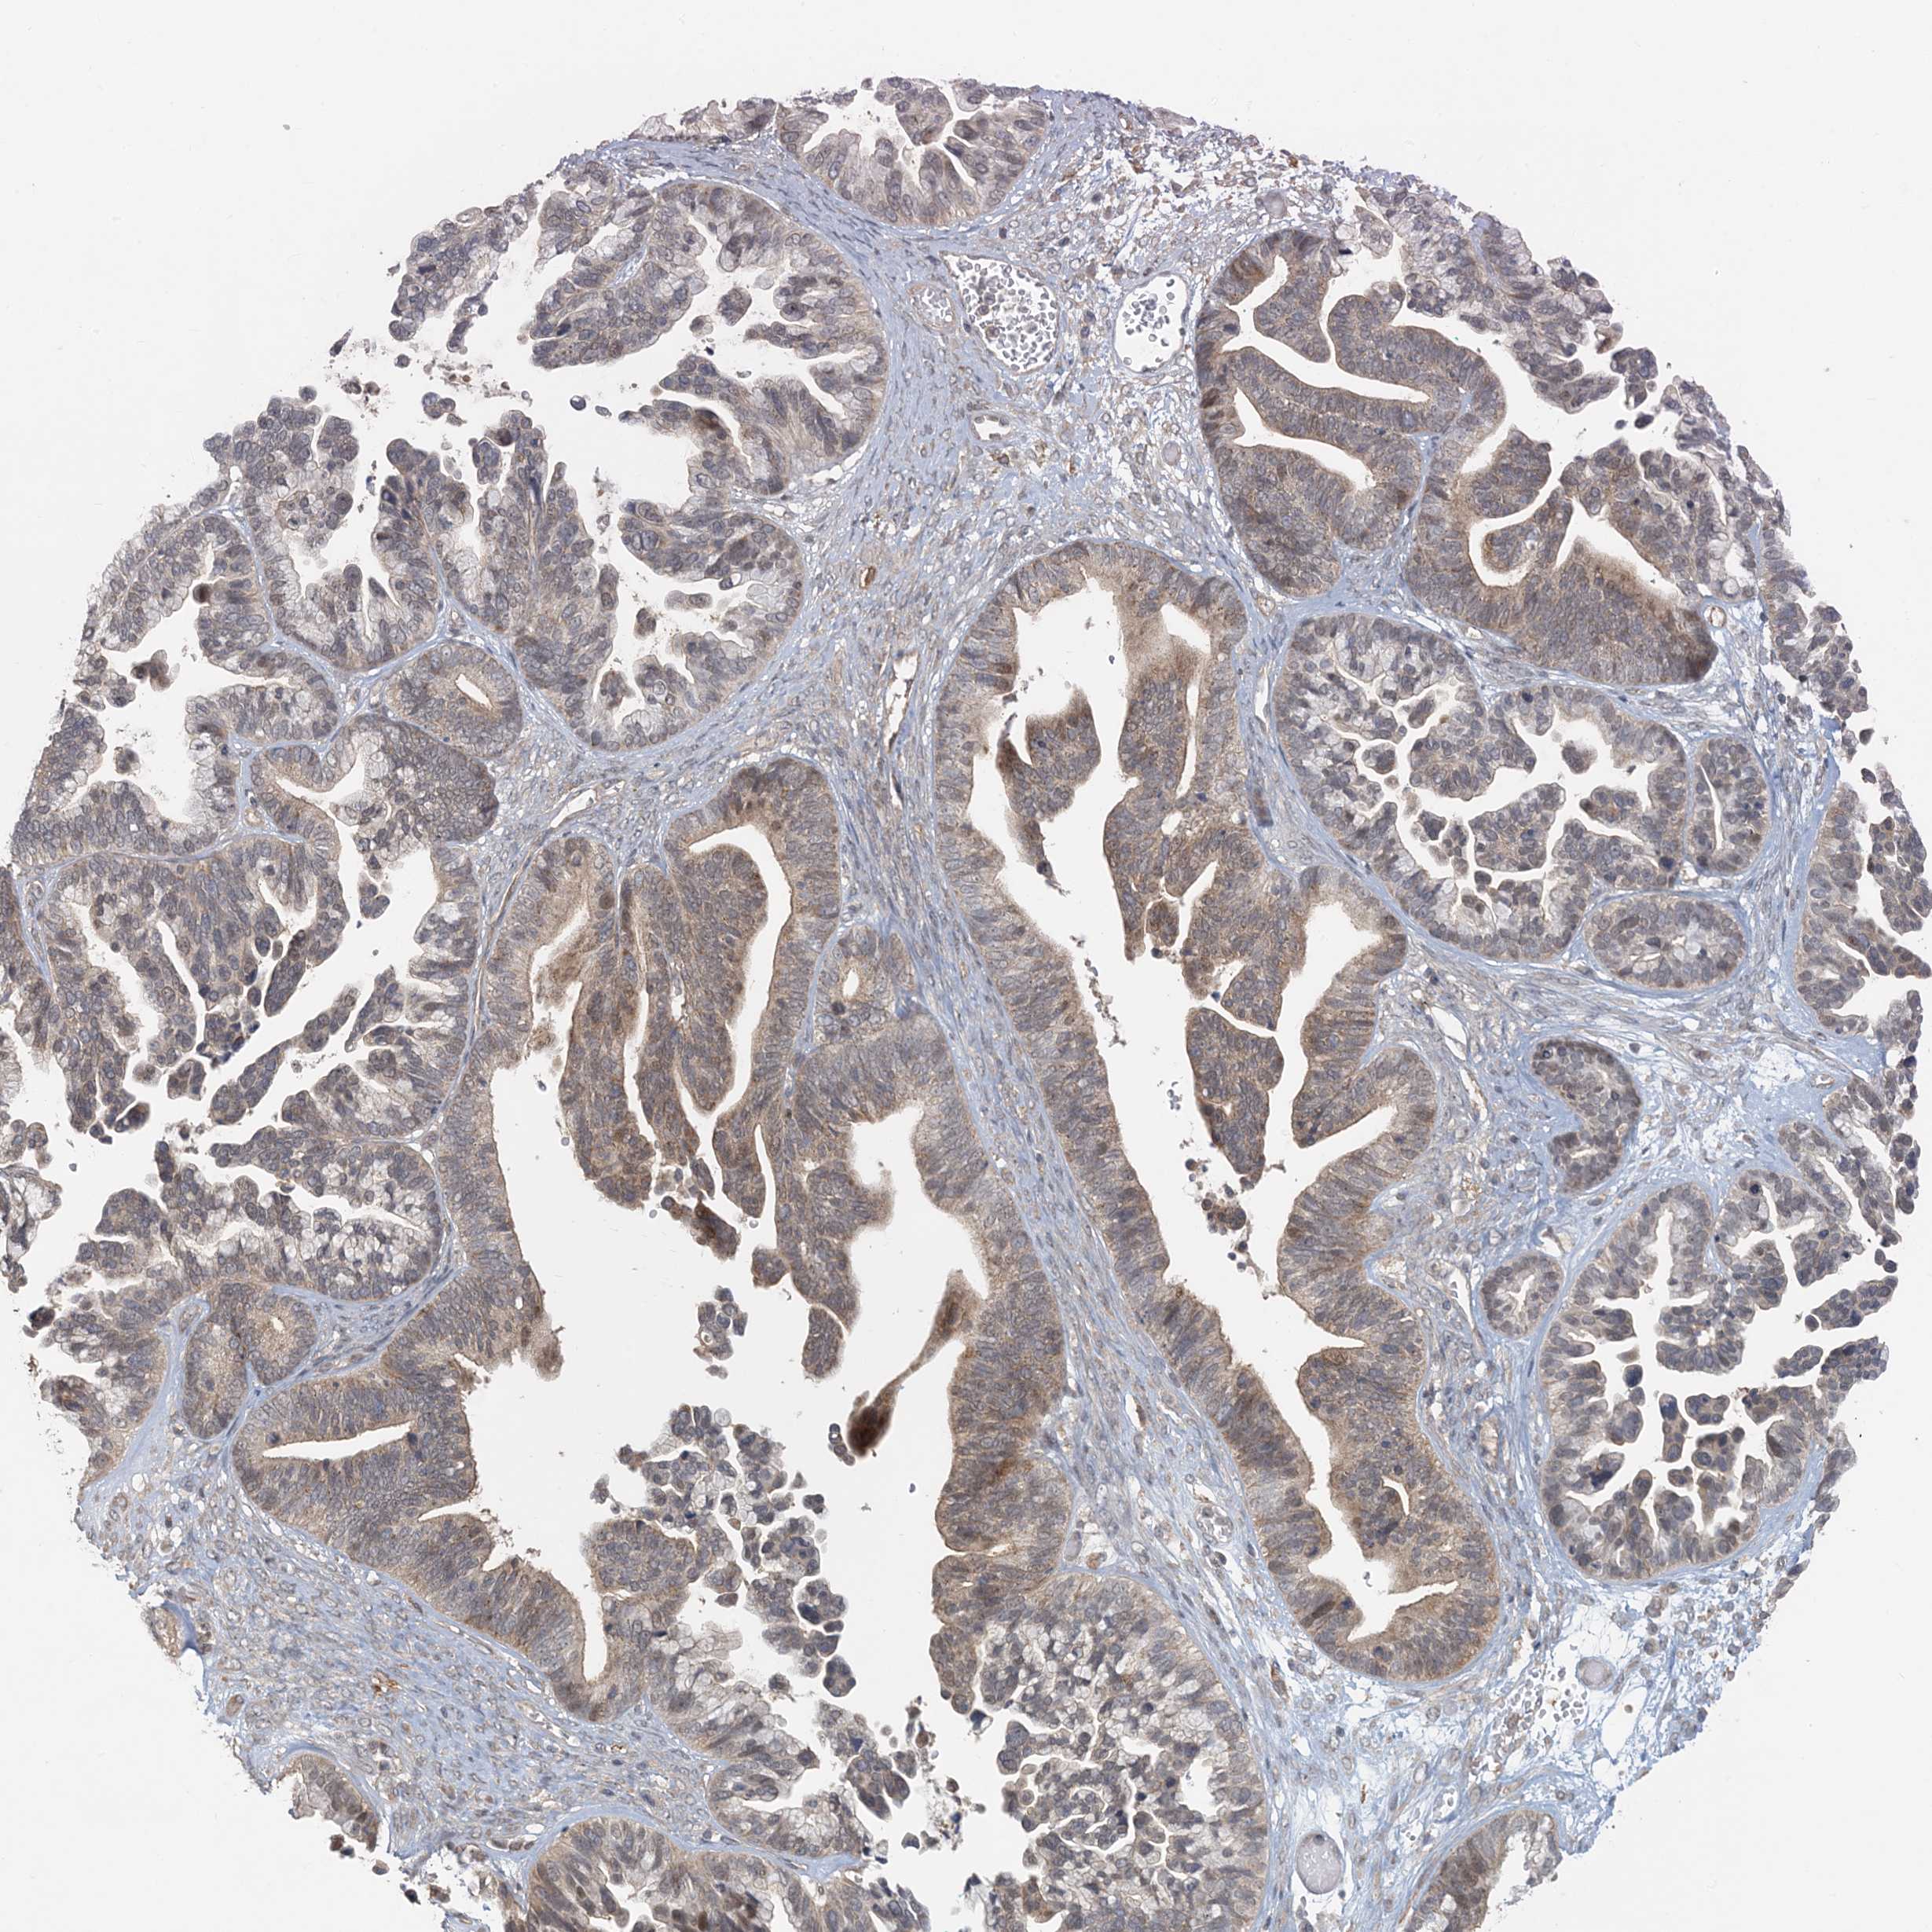

OVARIAN CANCER - Protein expressioni

A mouse-over function shows sample information and annotation data. Click on an image to view it in a full screen mode. Samples can be filtered based on level of antibody staining by selecting one or several of the following categories: high, medium, low and not detected. The assay and annotation is described here.

Note that samples used for immunohistochemistry by the Human Protein Atlas do not correspond to samples in the TCGA dataset.

Antibody stainingi

Antibody staining in the annotated cell types in the current human tissue is reported as not detected, low, medium, or high, based on conventional immunohistochemistry profiling in selected tissues. This score is based on the combination of the staining intensity and fraction of stained cells.

Each image is clickable and will lead to virtual microscopy that enables deeper exploration of all samples and also displays staining intensity scores, fraction scores and subcellular localization as well as patient and tissue information for each sample.

Antibody HPA034785

Antibody HPA034786

Cystadenocarcinoma, serous, NOS

Carcinoma, endometroid

Cystadenocarcinoma, mucinous, NOS

Carcinoma, NOS